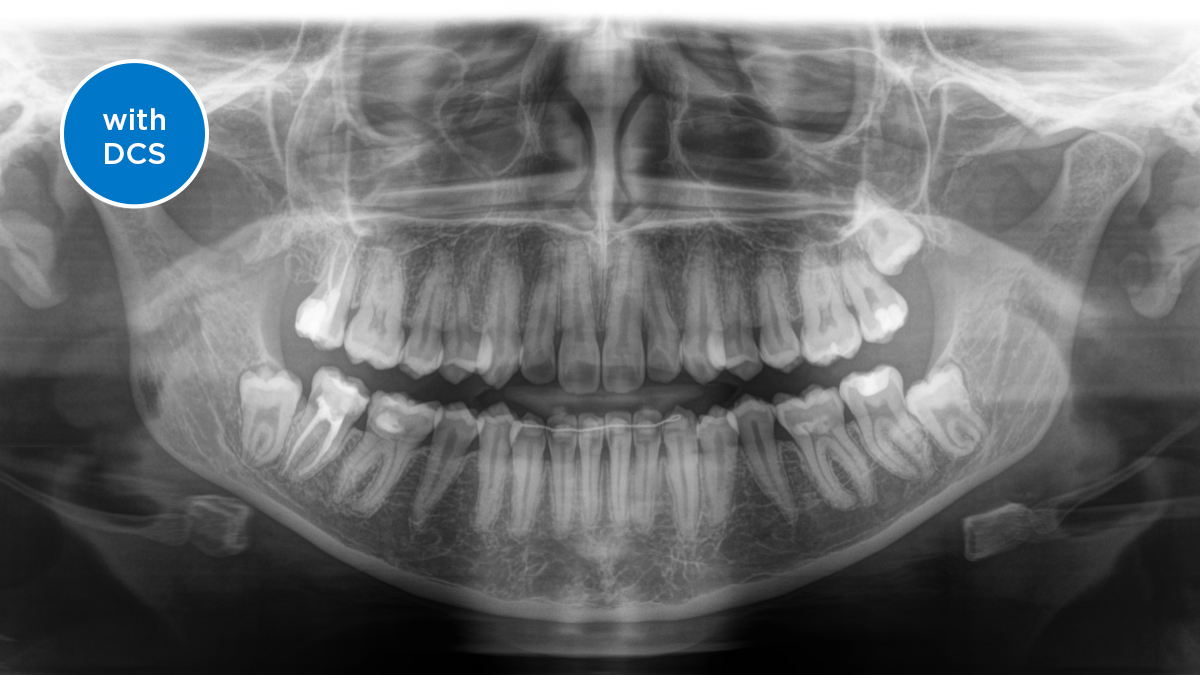

El sensor de conversión directa (Direct Conversion Sensor, DCS) ha revolucionado el estándar de la imagen panorámica. Las imágenes radiológicas se convierten directamente en señales eléctricas. Por lo tanto, no hay pérdida de señal debido a conversión de la luz, como es el caso de los sistemas convencionales. El resultado: imágenes con un alto nivel de nitidez y contraste, incluso con una dosis de radiación extremadamente baja. Para obtener información de diagnóstico precisa a fin de apoyar el tratamiento objetivo.

La imagen a continuación muestra una radiografía panorámica con y sin tecnología DCS. Usando la flecha, arrastre el control a través de la imagen para ver la diferencia que el sensor de conversión directa hace con la calidad de la imagen y las posibilidades de diagnóstico.